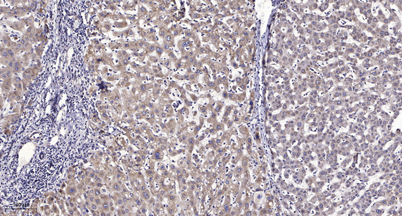

Product name: LOK rabbit pAb

Dilutions: WB 1:500-2000;IHC-p 1:50-300; ELISA 2000-20000